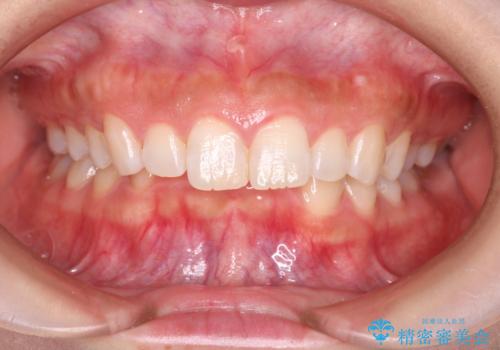

【出っ歯(飛び出した前歯)・がたつきでお悩みの方必見】インビザライン矯正の症例

![[ 出っ歯を治したい ] マウスピース矯正での上顎前突治療の症例 治療前](https://seimitsushinbi.jp/wp/wp-content/uploads/2022/03/IMG_9997-3-500x350.jpg?v=1648378247)

![[ 出っ歯を治したい ] マウスピース矯正での上顎前突治療の症例 治療後](https://seimitsushinbi.jp/wp/wp-content/uploads/2022/03/IMG_6262-500x350.jpg?v=1648378353)